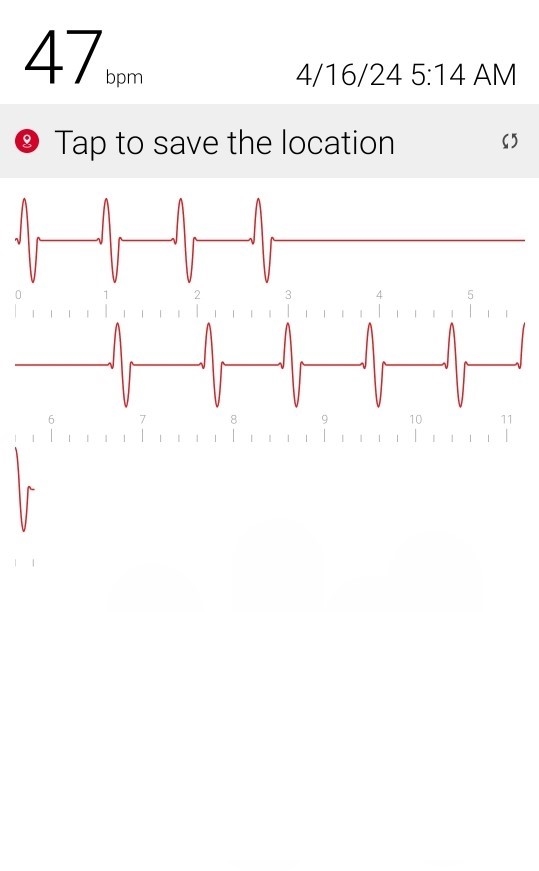

Initial ID consult diagnosed local tetanus based on clinical symptoms and recommended oral Metronidazole 500mg every 6 hours as an outpatient. Autonomic involvement developed with tachycardia and cardiac arrhythmia, along with episodes of sudden sweating. Loud noises made twitching/spasms worsen. Intermittent twitching continued to be present bilaterally in the body, face, jaw & tongue. Symptoms were suppressible with benzodiazepine. Tetanus IM IG 500 IU was recommended and obtained. After initial 2 week course of metronidazole was discontinued symptoms worsened again when patient would walk. Multiple trials of oral Metronidazole 500mg every 6 hours were attempted with some improvement while on the antibiotic but then return and worsening of symptoms again once antibiotic was discontinued.

incrementally, then once twitching had reached the spinal level, muscle twitching spread to the bilateral muscles of the body with cardiac arrhythmia & autonomic involvement/ sweating. A trial of antibiotic Keflex (cephalexin ) was suggested, which only at high dose (1000mg PO every 6 hours), helped keep spasms localized to the left foot mostly but symptoms would worsen and generalize if antibiotic Keflex (cephalexin) was stopped for more than 2 days. Benzodiazepine was increased to every q6 hours to reduce muscle twitching that had become constant in the left foot. Symptoms improve when patient does not walk or avoids any pressure or bending of left big toe and symptoms worsen when patient walks or stops antibiotic and has been unable to stop antibiotic for the past year and a half without worsening of symptoms. When antibiotic is stopped for 2 days bilateral jaws begin to snap shut intermittently involuntarily and cardiac arrhythmia/ heart block reoccurs. Symptoms worsen further after 4 days off antibiotic. Local

Oral Keflex (cephalexin) 1000mg 4 times a day & IM Bicillin LA 2.4 million units 3 times a week were restarted with improvement in bilateral body muscle twitching but twitching / spasms locally in the left toes and foot continued. This regimen was continued for 7 weeks. One day after discontinuing oral Keflex (cephalexin) (and 3 days after the last bicillin IM shot) spasms again began at the left big toe, left toes and left foot, progressed up the left leg to the left gluteal muscles and again once the spinal level was reached spasms spread to the right side of the body and then upper body and by 1 and 1/2 days after all antibiotic was discontinued, arrhythmia/heart block began again. Oral Keflex 1000mg 4 times a day was restarted (cephalexin). Benzodiazepines had been continued throughout.

3) Cardiac Arrhythmia / Heart Block occurs during generalizations

When antibiotic is discontinued or with increased walking, rhythm returns to normal when antibiotic is restarted after a few days.